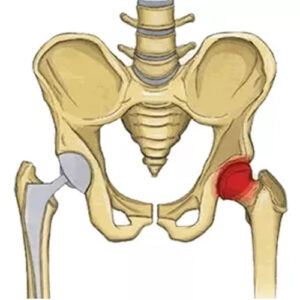

Kalçanın eski gücüne ve hareketlerine geri kavuşması için kalça protezi ameliyatı sonrası fizik tedavi önerilmektedir. Fizik tedavi yaralanma ve travmalar sonrası vücudun bazı fonksiyonel hareketlerini kaybetmesi sonucu geri kazandırılması için yapılan bir takım egzersizlere verilen isimdir. Fizik tedavi, kalça protezi ameliyatı olan hastaların yürüme sürecinin hızlandırılması ve proteze adaptasyon sağlayabilmesi için oldukça önem taşımaktadır. Kalça protezi ameliyatı sonrası fizik tedavi hareketleri hakkında merak ettiğiniz tüm soruların yanıtlarını öğrenmek için okumaya devam edebilirsiniz.

Kalça Protezi Ameliyatı Sonrası Fizik Tedavi Hareketleri

Kalça Protezi Ameliyatı Sonrası Fizik Tedavi Hareketleri